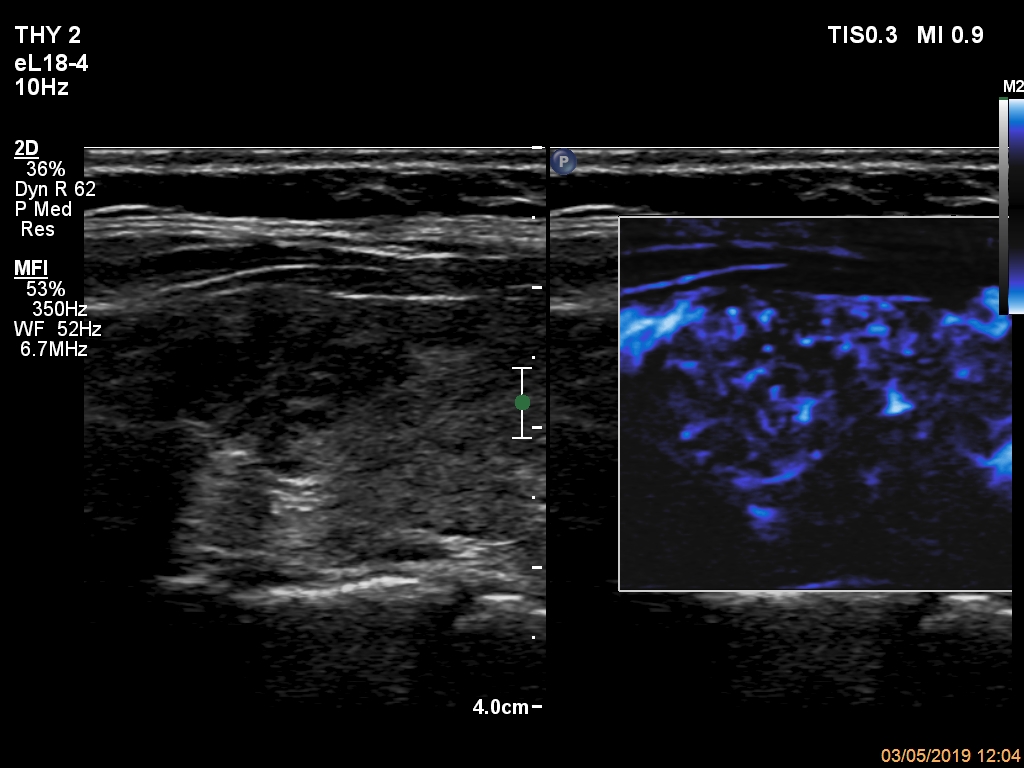

Extrathyroidal spread - case 2138 (ultrasonographic picture 8)

Left lobe, longitudinal scan, microflow imaging. The vascularization of the upper discrete hypoechoic area (left in the image) does not differ from that of the other parts of the lobe.